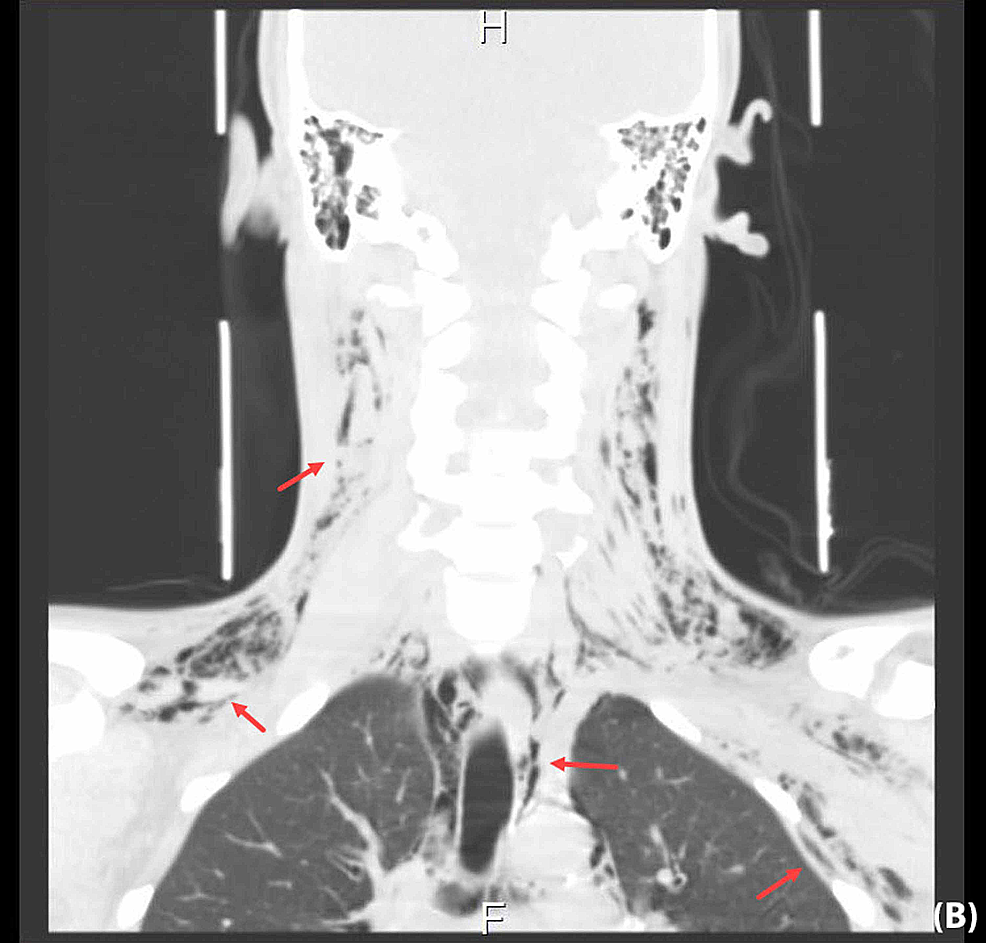

(PDF) Spontaneous pneumomediastinum with subcutaneous emphysema in a Youngest Emphysema Case Emphysema is a type of. Emphysema can cause chest tightness, shortness of breath, and fatigue. Cases had moderate airflow limitation (fev1 71.3±20.8%) but were often symptomatic, used healthcare resources frequently, had air trapping (residual volume 150.6±55.5% ref.), had reduced. Using cox proportional model, we determined the comorbidities associated with mortality risk and generated comorbidomes for. Youngest Emphysema Case.

Cureus Spontaneous Subcutaneous Emphysema and Pneumomediastinum Youngest Emphysema Case Emphysema is a type of. Using cox proportional model, we determined the comorbidities associated with mortality risk and generated comorbidomes for. Cases had moderate airflow limitation (fev1 71.3±20.8%) but were often symptomatic, used healthcare resources frequently, had air trapping (residual volume 150.6±55.5% ref.), had reduced. Emphysema can cause chest tightness, shortness of breath, and fatigue. Youngest Emphysema Case.